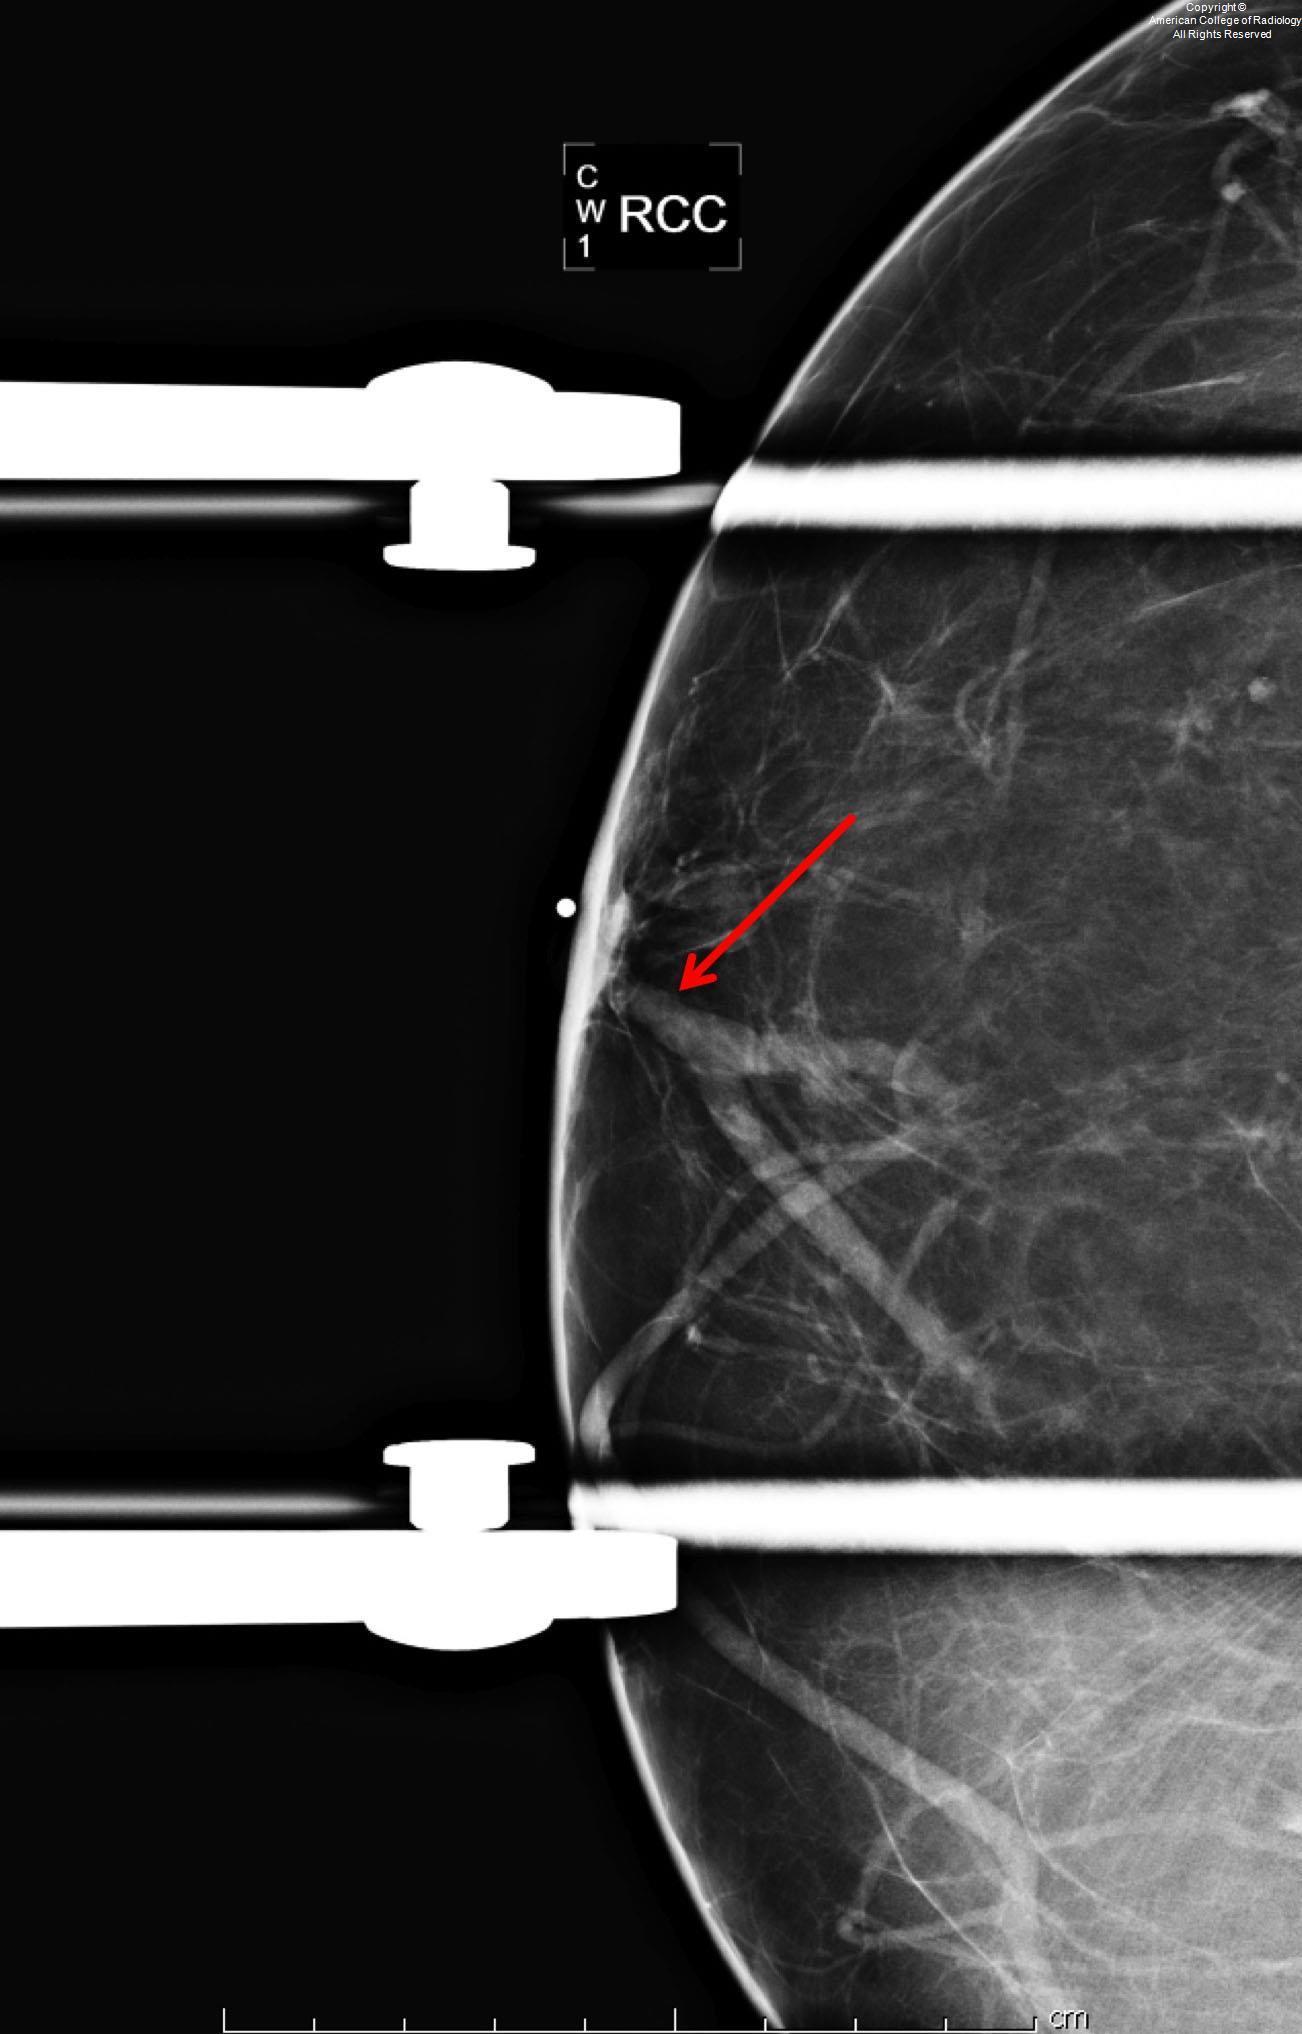

Dilated duct due to intraductal papilloma